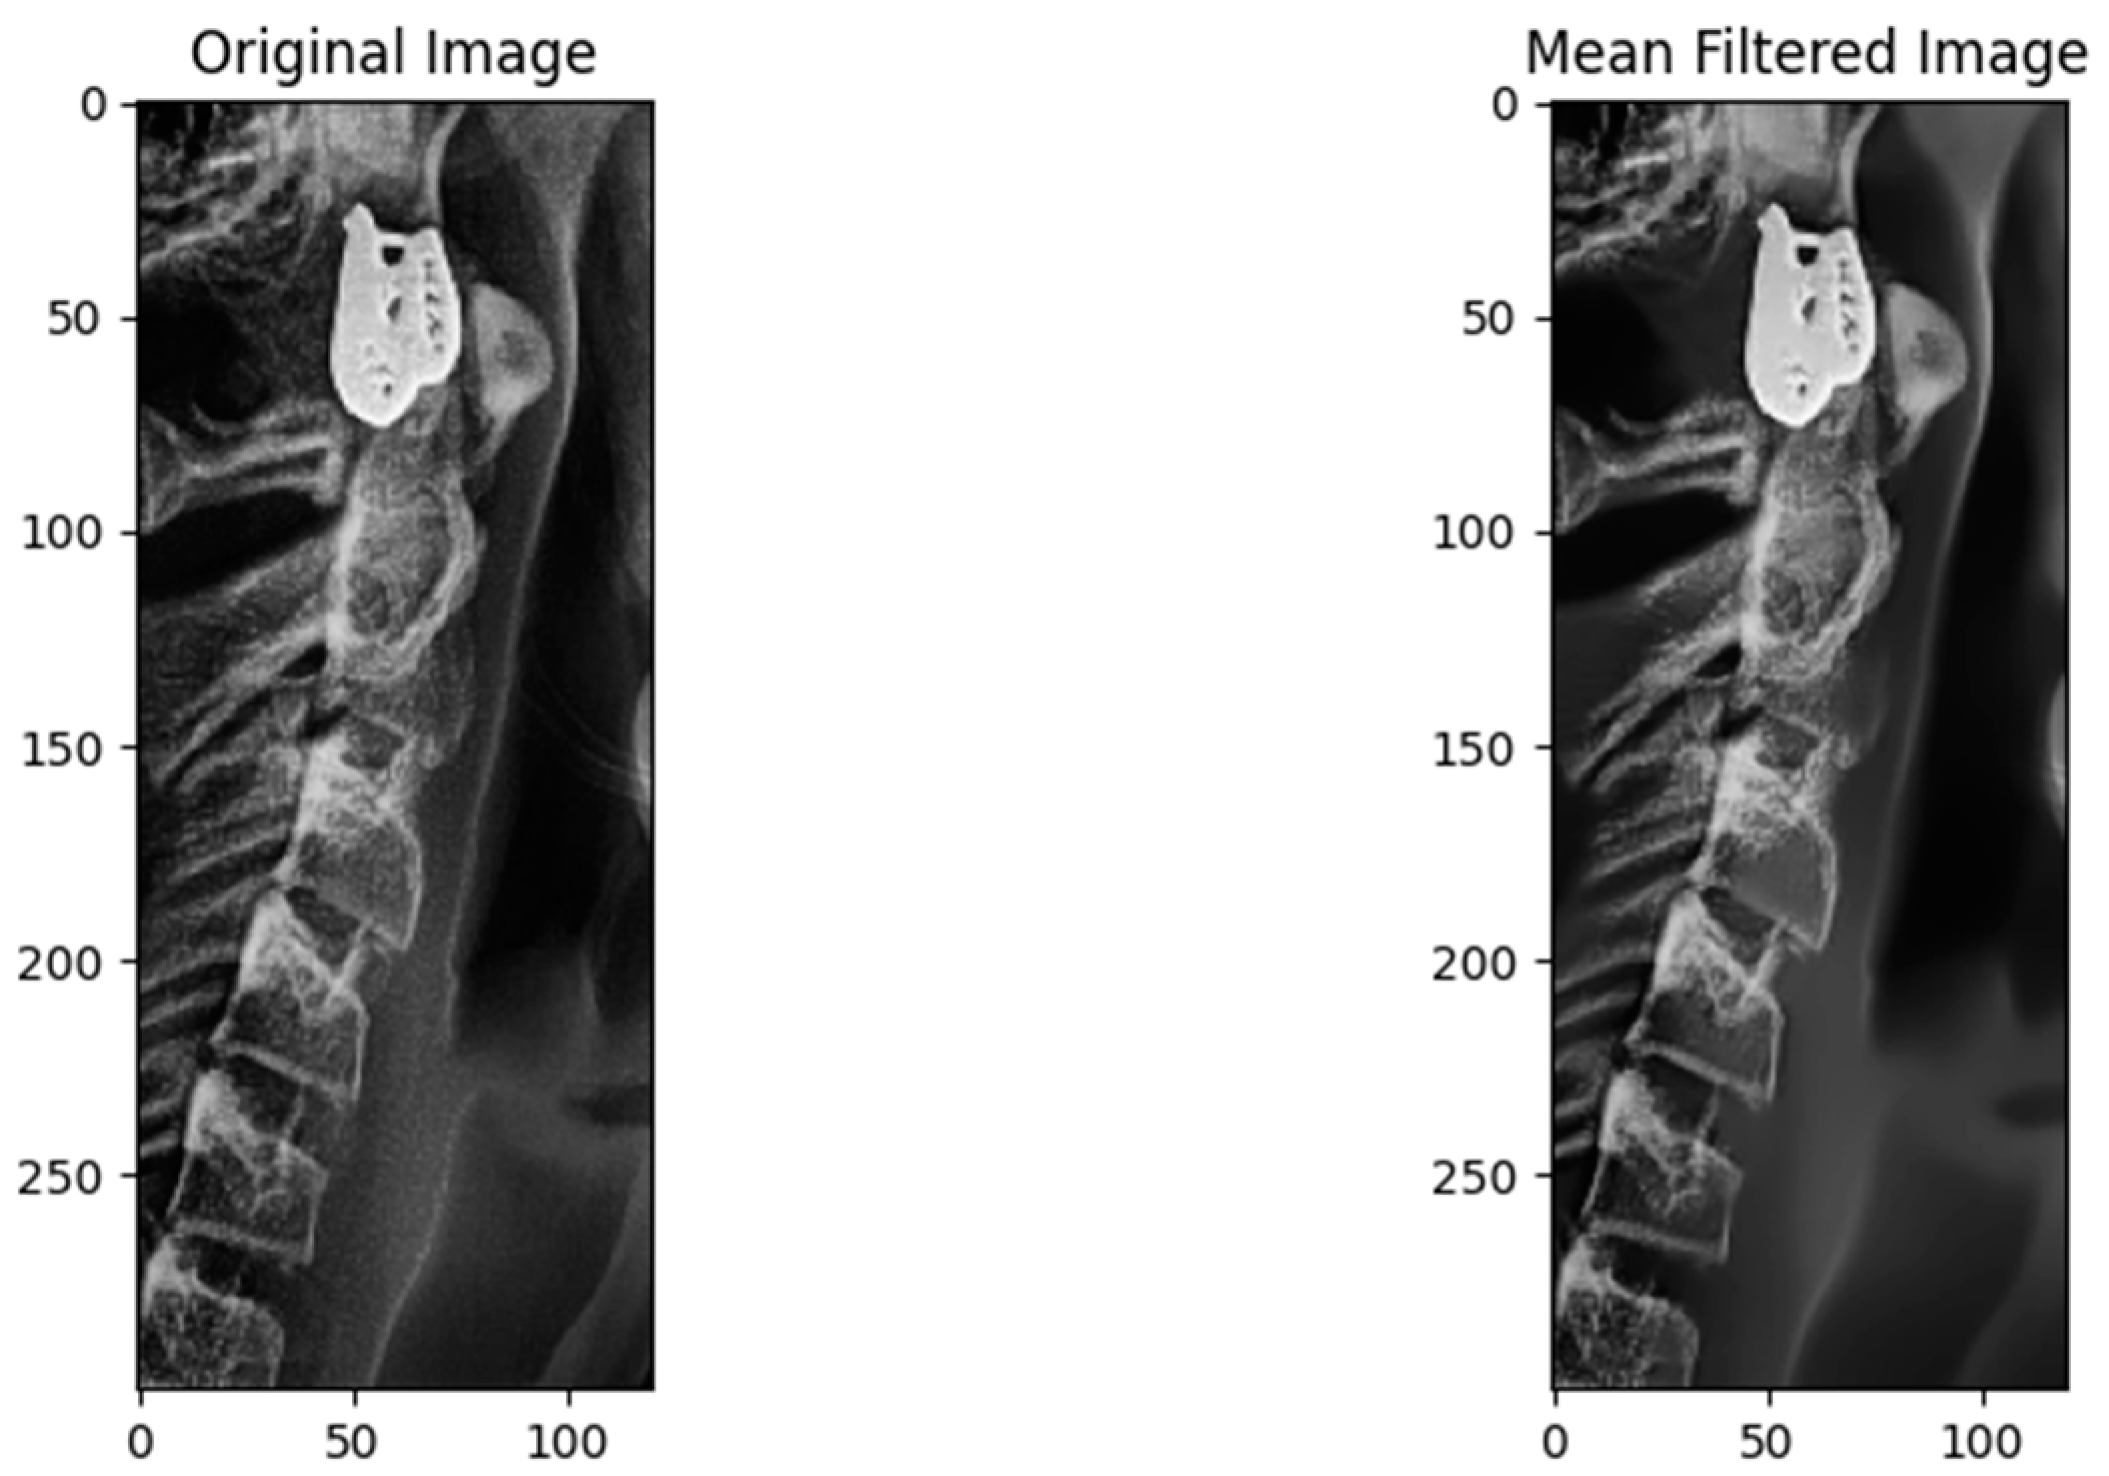

2.3.2. Preprocessing Step

2.3.3. Augmentation Step